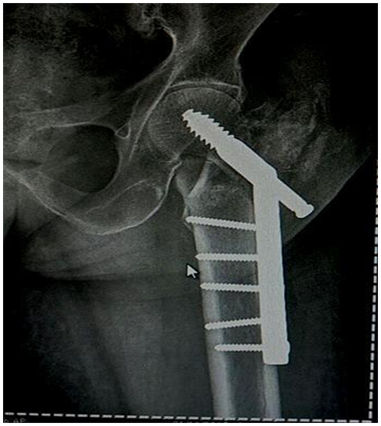

Hip pin and compression screw

Hip pin to be shorter than compression screw. Deep positioning to maintain tip apex distance. Head screws to be tightened alternately for compression. But may sink inside bone (Figure 31,32).

Figure 31 Hip pin to be shorter than compression screw. Deep positioning to maintain tip apex distance.

Figure 32 Head screws to be tightened alternately for compression. But may sink inside bone.